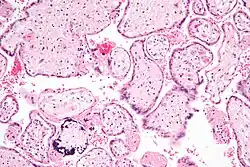

Micrograph of a cytomegalovirus (CMV) infection of the placenta (CMV placentitis). The characteristic large nucleus of a CMV-infected cell is seen off-centre at the bottom-right of the image. H&E stain.